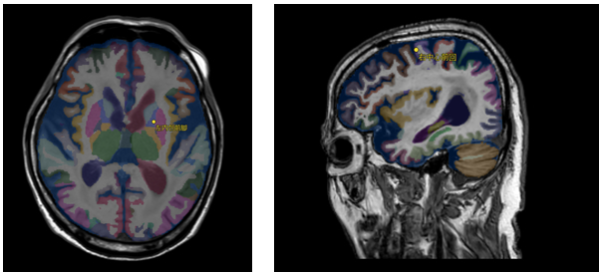

② 脳区域ラベリング

「SYNAPSE SAI viewer」に既載の「脳区域ラベリング」(頭部CT画像において頭部を34区域にラベリングする機能)に続き、MRI画像にも対応した「脳区域ラベリング(MR)」を新たに提供する。本機能では、読影レポートに記載頻度の高い「中心前回」「中心後回」や、脳梗塞や脳出血、白質病変の好発部位である「内包前脚」「内包後脚」などを含め、非造影T1強調画像から脳111区域のラベリングを可能にする。医師は画像上で特定の脳領域を容易に同定することができるため、脳疾患の読影支援に繋がることが期待される。

また、ラベリングした各領域の体積を算出・表示することも可能で、指定した脳領域の経時変化をグラフ表示することも可能である。